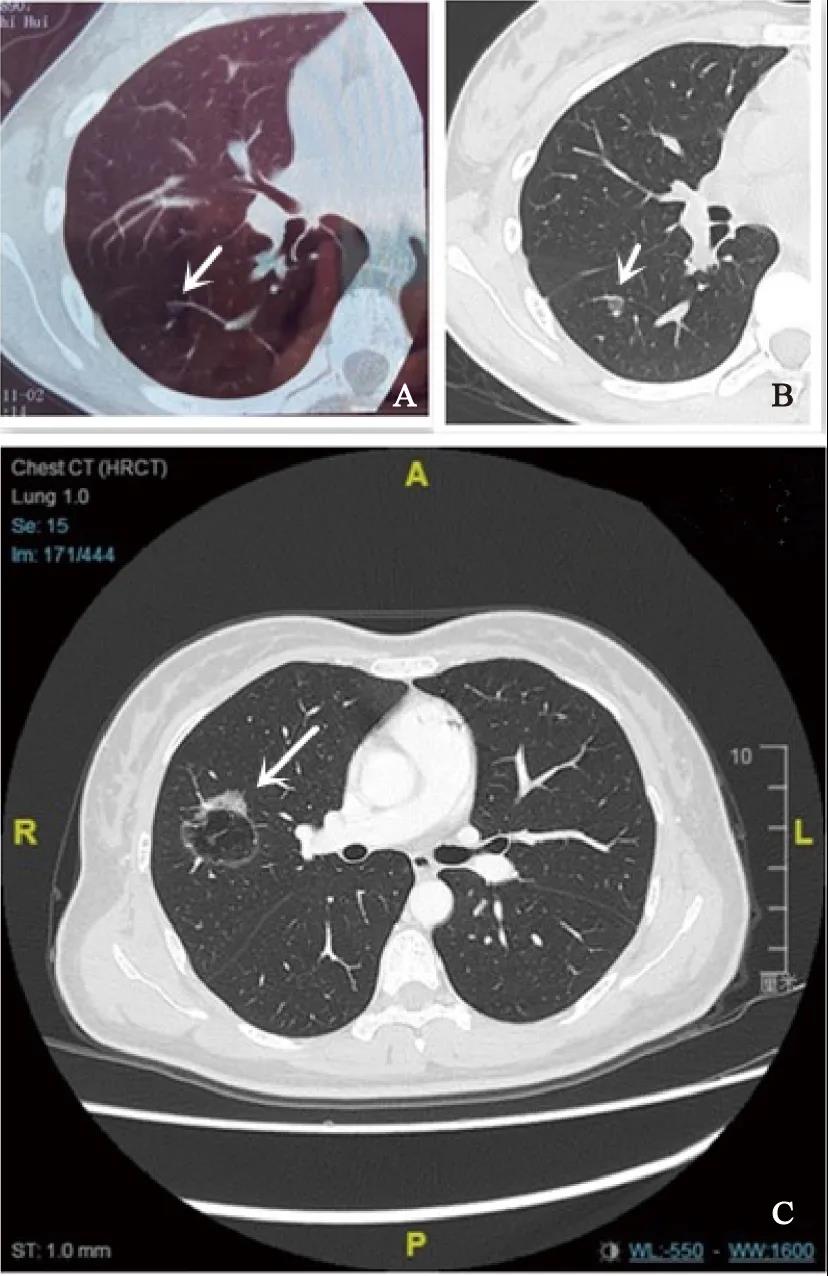

肺癌是全球最常见的癌症之一,其发病率与死亡率均居恶性肿瘤首位。如今,早期肺癌的检出率在增加,但肺癌的死亡率依然居高不下。 山东第一医科大学第三附属医院副...